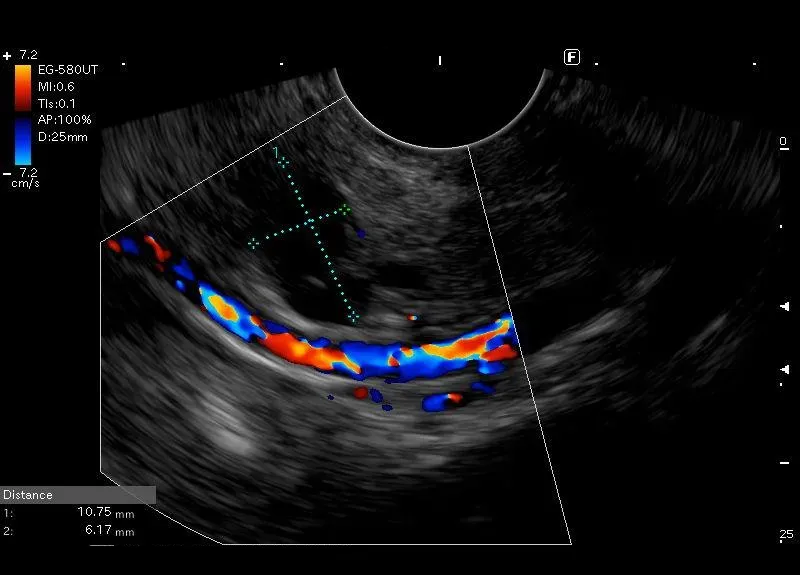

Widoczne na granicy głowy i trzonu trzustki na odcinku około 11 mm, torbielowate poszerzenie do 6mm przewodu Wirsunga - obraz może odpowiadać MD -IPMN ( main duct IPMN).